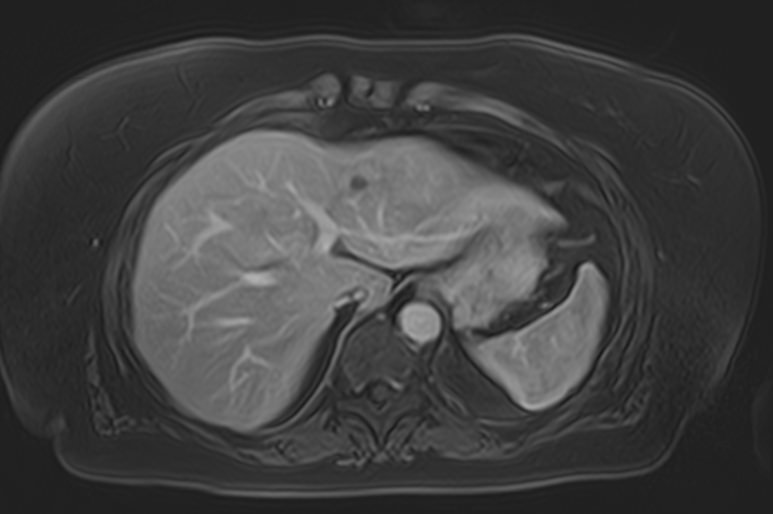

Магнитно-резонансная томография брюшной полости является наиболее информативной безопасной и эффективной методикой обследования внутренних органов. Метод позволяет проводить дифференциальную диагностику в сложных клинических случаях. Особенно это важно при противоречивых и неоднозначных данных, полученных при проведении УЗИ, рентгенографии, КТ или других обследованиях.

Методика МРТ основана на применении внешнего магнитного поля и отличается точностью и достоверностью полученных данных. Отсутствие вредного рентгеновского излучения делает процедуру безопасной и позволяет при необходимости проводить томографию несколько раз в течение короткого периода времени. Это бывает важно, например, для оценки динамики состояния патологических изменений в органах на фоне лечения.

Для расширения возможностей диагностики, при необходимости уточнения характера патологических изменений, в случае подозрения на опухолевый процесс, дополнительно применяется контрастное усиление.

Для этого в вену вводится контрастный препарат, содержащий металл гадолиний (Магневист, Гадовист, Омнискан и др). Степень и характер накопления контрастного препарата в органах и тканях позволяет различать патологические процессы. Это дает возможность, в частности, диагностировать патологические очаги минимальных размеров, что бывает особенно важно в ранней диагностике опухолей.

В клинике «Доступная медицина» МР томография проводится на новейшем высокопольном томографе экспертного класса TOSHIBA VANTAGE TITAN 1,5 Тесла. Высокая индукция магнитного поля обеспечивает повышенную четкость изображений при проведении обзорной МРТ брюшной полости, что гарантирует точность и эффективность диагностики заболеваний печени, желчного пузыря, поджелудочной железы и селезенки. Аппарат послойно сканирует исследуемую область с шагом от 1 мм в различных плоскостях, затем трансформирует результаты в трехмерные изображения превосходного качества. Для уточнения характера патологических изменений одного из органов назначается прицельная МР томография данного органа.